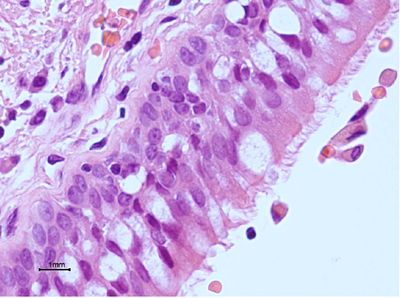

Hier ziet u een detail van de thrombo-embolus. Is er reeds sprake van organisatie?

Answer

• Ja

• Nee